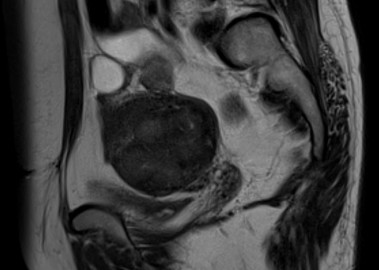

거대 자궁선근증 치료 사례